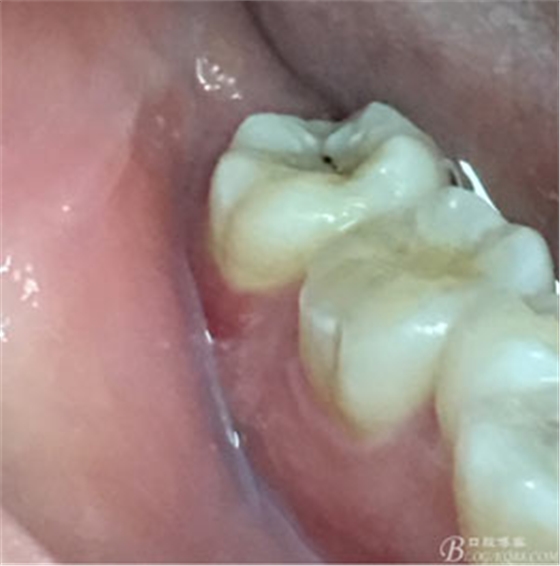

圖2.37牙冠基本完好,松動Ⅰ度。合面有一開髓孔被棉球覆蓋,頰側(cè)牙齦輕度紅腫。